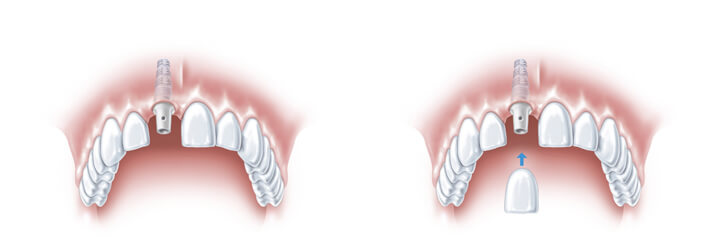

Auch größere Zahnlücken zwischen gesunden Zähnen können heute mit Zahnimplantaten versorgt werden. Dazu werden die Implantate an die Stelle der entfernten Zahnwurzeln gesetzt und später mit einer Brücke oder mit einzelnen Kronen vollendet.

Insbesondere bei Patienten, bei denen die Zähne endständig fehlen (Freiendsituation), also meist bei den hinteren Backenzähnen, empfehlen wir die Implantologie als Behandlungsmethode, damit ein herausnehmbarer Zahnersatz vermieden werden

kann. Bei einem reduzierten Restgebiss ist oft eine klassische Prothese nur als Kompromisslösung möglich. Durch Zahnimplantate kann man die notwendigen Pfeiler vermehren und so entweder einen festsitzenden Zahnersatz einsetzen oder einen

herausnehmbaren viel graziler und komfortabler (bspw. ohne Gaumenplatte) gestalten.